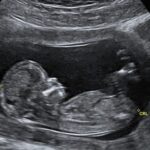

На ранних стадиях рак молочной железы может не вызывать никаких симптомов. Во многих случаях опухоль может быть слишком мала для ощущения, но аномалию все еще можно увидеть на маммографии. Если опухоль может ощущаться, первым признаком обычно является новый комок в груди, которого раньше не было. Однако не все комки являются раком.